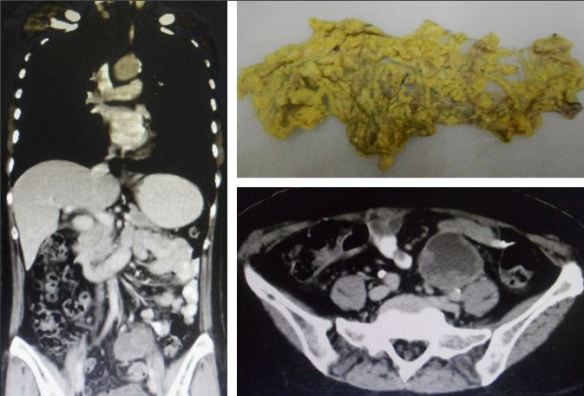

• In the pelvis, the uterus is markedly enlarged with extensive heterogenous soft tissues measuring 7 x 10 cm in maximal diameters, entirely consistent with endometrial tumour.

Conclusion: Intrauterine tumour. Poorly differentiated carcinoma favouring uterine origin. No evidence of tumour spread elsewhere.

A CT scan on 4 December 2017 showed cancer of the endometrium

Her medical report indicated, “in the pelvis, the uterus is markedly enlarged with extensive hetergenous soft tissues measuring 7 x 10 cm in maximal diameters, entirely consistent with endometrial tumour. Conclusion: Intrauterine tumour. Poorly differentiated carcinoma favouring uterine origin. No evidence of tumour spread elsewhere.”